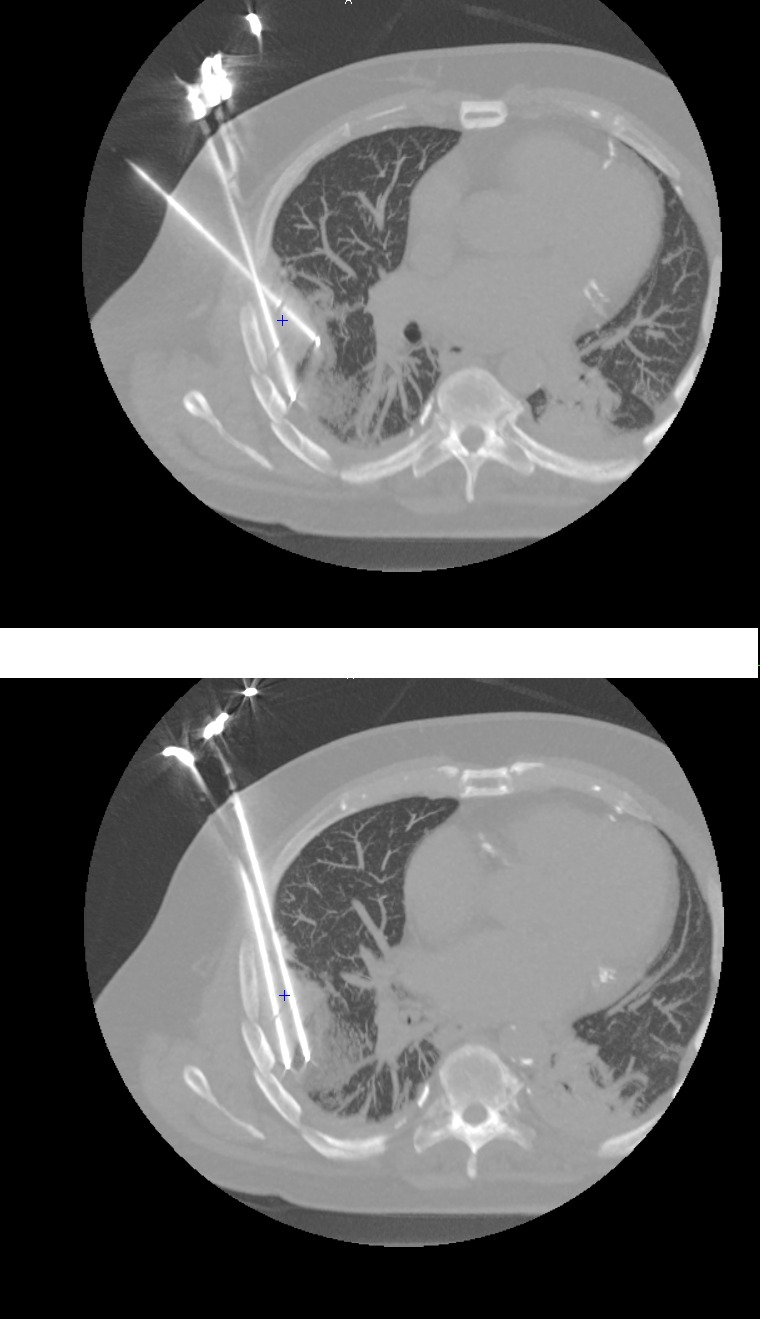

L'imagerie permet de guider le positionnement des aiguilles autour de la tumeur desmoïde, qui est logée entre les côtes et le poumon.   © CHU Helora

Après, on fait un suivi par imagerie à trois et à six mois, pour vérifier si le traitement a été suffisant ou s’il faut y revenir. Logiquement, les cellules dans la zone traitée sont mortes : on arrive à obtenir une bonne marge, et surtout on épargne les structures adjacentes (les nerfs, les vaisseaux) parce qu’on voit très bien où l’on va. Dans un cas comme celui de notre premier patient, chirurgicalement, il aurait probablement fallu enlever une côte, voire une partie de la plèvre : c’aurait été une opération très délabrante.